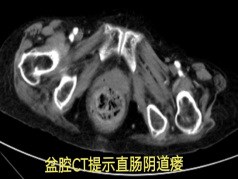

凌晨 1 点,88 岁的刘奶奶突发大量便血,胃肠·甲状腺外科接到紧急会诊呼叫。

在积极止血过程中,团队发现出血并非单纯的直肠肛门问题,怀疑可能合并阴道瘘。初步处理后,患者被转入胃肠甲状腺外科进一步诊治,最终确诊为直肠阴道瘘并局部感染出血。

然而,真正的挑战才刚刚开始:患者 20 多年前曾接受直肠肿瘤手术,此次手术方案的制定难度陡增。高龄、既往直肠癌手术史、阴道瘘感染、凶猛的出血——其中任何一项单独出现,都已属高危;此刻,却全部叠加在一起。

杨战锋主任建议启动"疑难病例云平台",共商手术预案。经北上广深多位专家线上会诊,最终探讨出最佳治疗方案。手术顺利完成后,患者平安度过危险期。